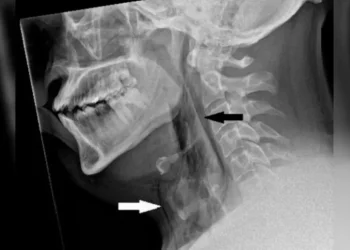

Saiba MaisMundo - Um paciente que não teve seu nome divulgado, teve sua traqueia rompida após tentar segurar seus espirros, pressionando...